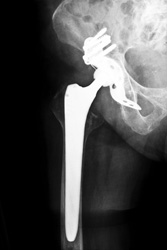

Una deludente percentuale di protesi impiantate durante la tradizionale sostituzione totale dell'anca (THR) cede entro i primi 16 - 20 anni. Ai pazienti più attivi con ossa sono di buona qualità, invece della THR, l'ortopedico potrebbe consigliare una procedura denominata protesi d'anca di superficie, che consente una maggiore preservazione di osso naturale all'interno e intorno all'articolazione e che garantisce una maggiore durata. Tale intervento implica la sostituzione della superficie danneggiata o malata dell'articolazione sferoidale nell'anca con una ricopertura metallica molto levigata, tramite l'intervento di superficie dell'anca metallo su metallo (MoM). Tuttavia, i referti che segnalano alti livelli di cobalto e cromo nel sangue e nel siero nei pazienti con dispositivi MoM hanno destato notevoli preoccupazioni sui loro effetti a lungo termine. Alcuni scienziati finanziati dall'UE si sono proposti di sviluppare una migliore protesi dell'anca, utilizzando ceramiche ad alte prestazioni con un grado elevato di resistenza alla compressione, resistenza all'usura e inerzia chimica. Il progetto ENDURE(si apre in una nuova finestra) ("Enhanced durability resurfacing endoprosthesis") si è posto l'ambizioso obiettivo di una durata ultratrentennale delle protesi. Per poter giungere a una protesi d'anca di superficie con ceramica su polimero, i ricercatori si sono rivolti alle bioceramiche composite a matrice di allumina e al poli-eter-eter-chetone rinforzato con fibra di carbonio. Hanno sviluppato nuovi metodi economici per processare i polimeri e, per giungere ai progetti definitivi, hanno impiegato ampiamente test teorici e sperimentali. Il sistema e il suo impianto hanno ottenuto esiti positivi nei test e nelle dimostrazioni compiute da chirurghi specializzati che hanno lavorato su cadaveri. La pubblicazione preliminare di risultati sul sito web del progetto ha determinato una frenesia di domande e interesse espresso, conferendo slancio all'accelerazione del processo relativo alle sperimentazioni cliniche. La commercializzazione rivestirà un'enorme importanza per l'economia dell'UE e per la competitività delle sue piccole e medie imprese che lavorano in questo campo. La diminuzione degli interventi di revisione chirurgica consentiranno anche eccezionali risparmi per il sistema sanitario e, ovviamente, miglioreranno notevolmente la qualità della vita dei molti pazienti di ogni età sottoposti a intervento di sostituzione d'anca.